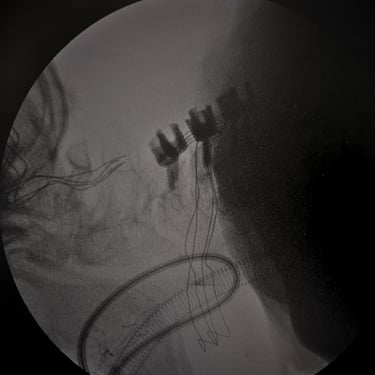

🧠Hidrocefalia Posthemoventricular: Tratamiento con Derivación Ventriculoperitoneal.

La hidrocefalia posthemoventricular requiere manejo quirúrgico en casos sintomáticos. La derivación ventriculoperitoneal permite controlar la presión intracraneal, mejorar la función neurológica y prevenir el daño cerebral progresivo.